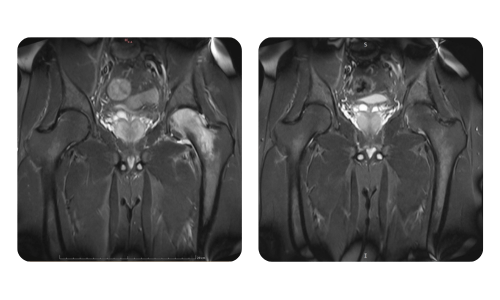

I progressi dei nostri pazienti, misurati prima e dopo la terapia iperbarica, riflettono l'efficacia e l'impatto positivo del trattamento. Scopri i risultati documentati della terapia iperbarica presso la clinica Hyperbarium Oradea, basati su valutazioni cliniche e dati oggettivi che evidenziano miglioramenti significativi in diverse condizioni.